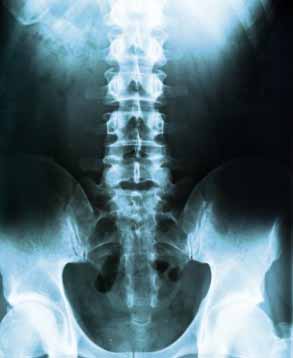

Sacroiliac Joint, Back Problems

Studies have found that 20 to 25% of all chronic lower back pain comes not from the spine but from the sacroliac, or SI Joint, which bears and transfers weight and movement from your upper body to your legs. When the ligaments wear out and the SI joint becomes unstable, it can generate a similar kind of sharp back pain -- or sciatica-like pain down your leg -- as a ruptured disc.

Back injuries result from damage, wear, or trauma to the bones, muscles, or other tissues of the back. Common back injuries include sprains and strains, herniated disks, and fractured vertebrae. The lumbar is often the site of back pain. The area is susceptible because of its flexibility and the amount of body weight it regularly bears. It is estimated that low-back pain may affect as much as 50 to 70 percent of the general population in the United States.